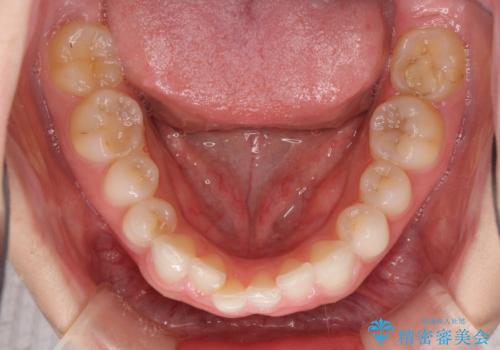

治療前、下顎前歯はほとんど見えない咬み合わせでしたが、矯正治療によりディープバイトが改善されました。

矯正治療中に前歯2本のクラウンは外れてしまい、途中仮歯に替える必要があったので期間は掛かりましたが、歯列も整い、負担のかからない咬み合わせを達成することができました。